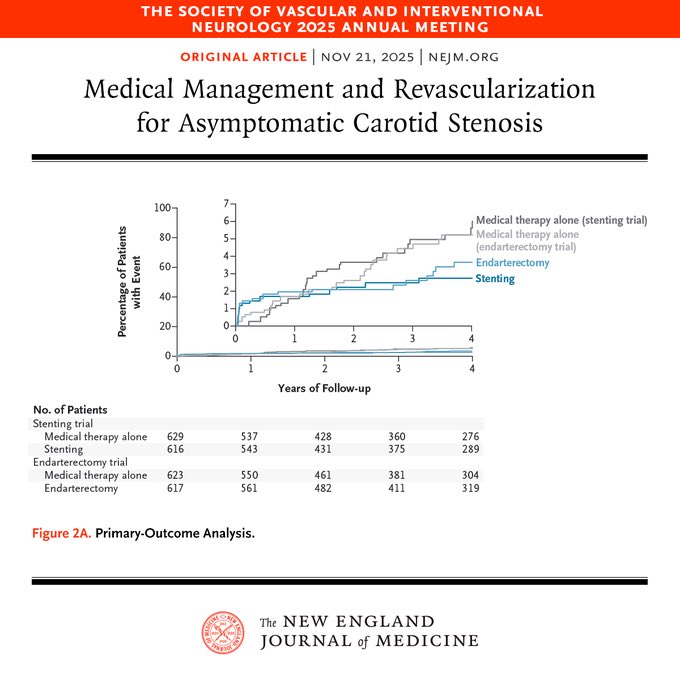

🗓️ 23/11/2025 ✅ Repasamos en 3TuitX #LaSemanaenCardioX‼️ 💚 Abrimos mini🧵 y pregunta #CardioEd 🤔 Trat médico óptimo vs endarterectomia vs stent en estenosis carotidea ⁉️ ✅ CREST-2 🔝 Beneficio trat médico óptimo + stent en estenosis carotidea

Presented at #SVIN25: CREST-2: In high-grade asymptomatic carotid stenosis, addition of stenting to medical therapy led to a lower risk of stroke over a 4-year period. Endarterectomy did not lead to a significant benefit. Full results: nej.md/3LK9kst Editorial:…